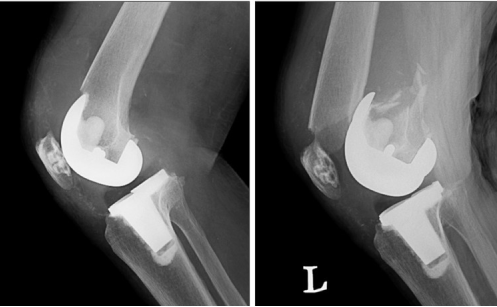

Total joint replacement surgery can restore mobility and reduce chronic